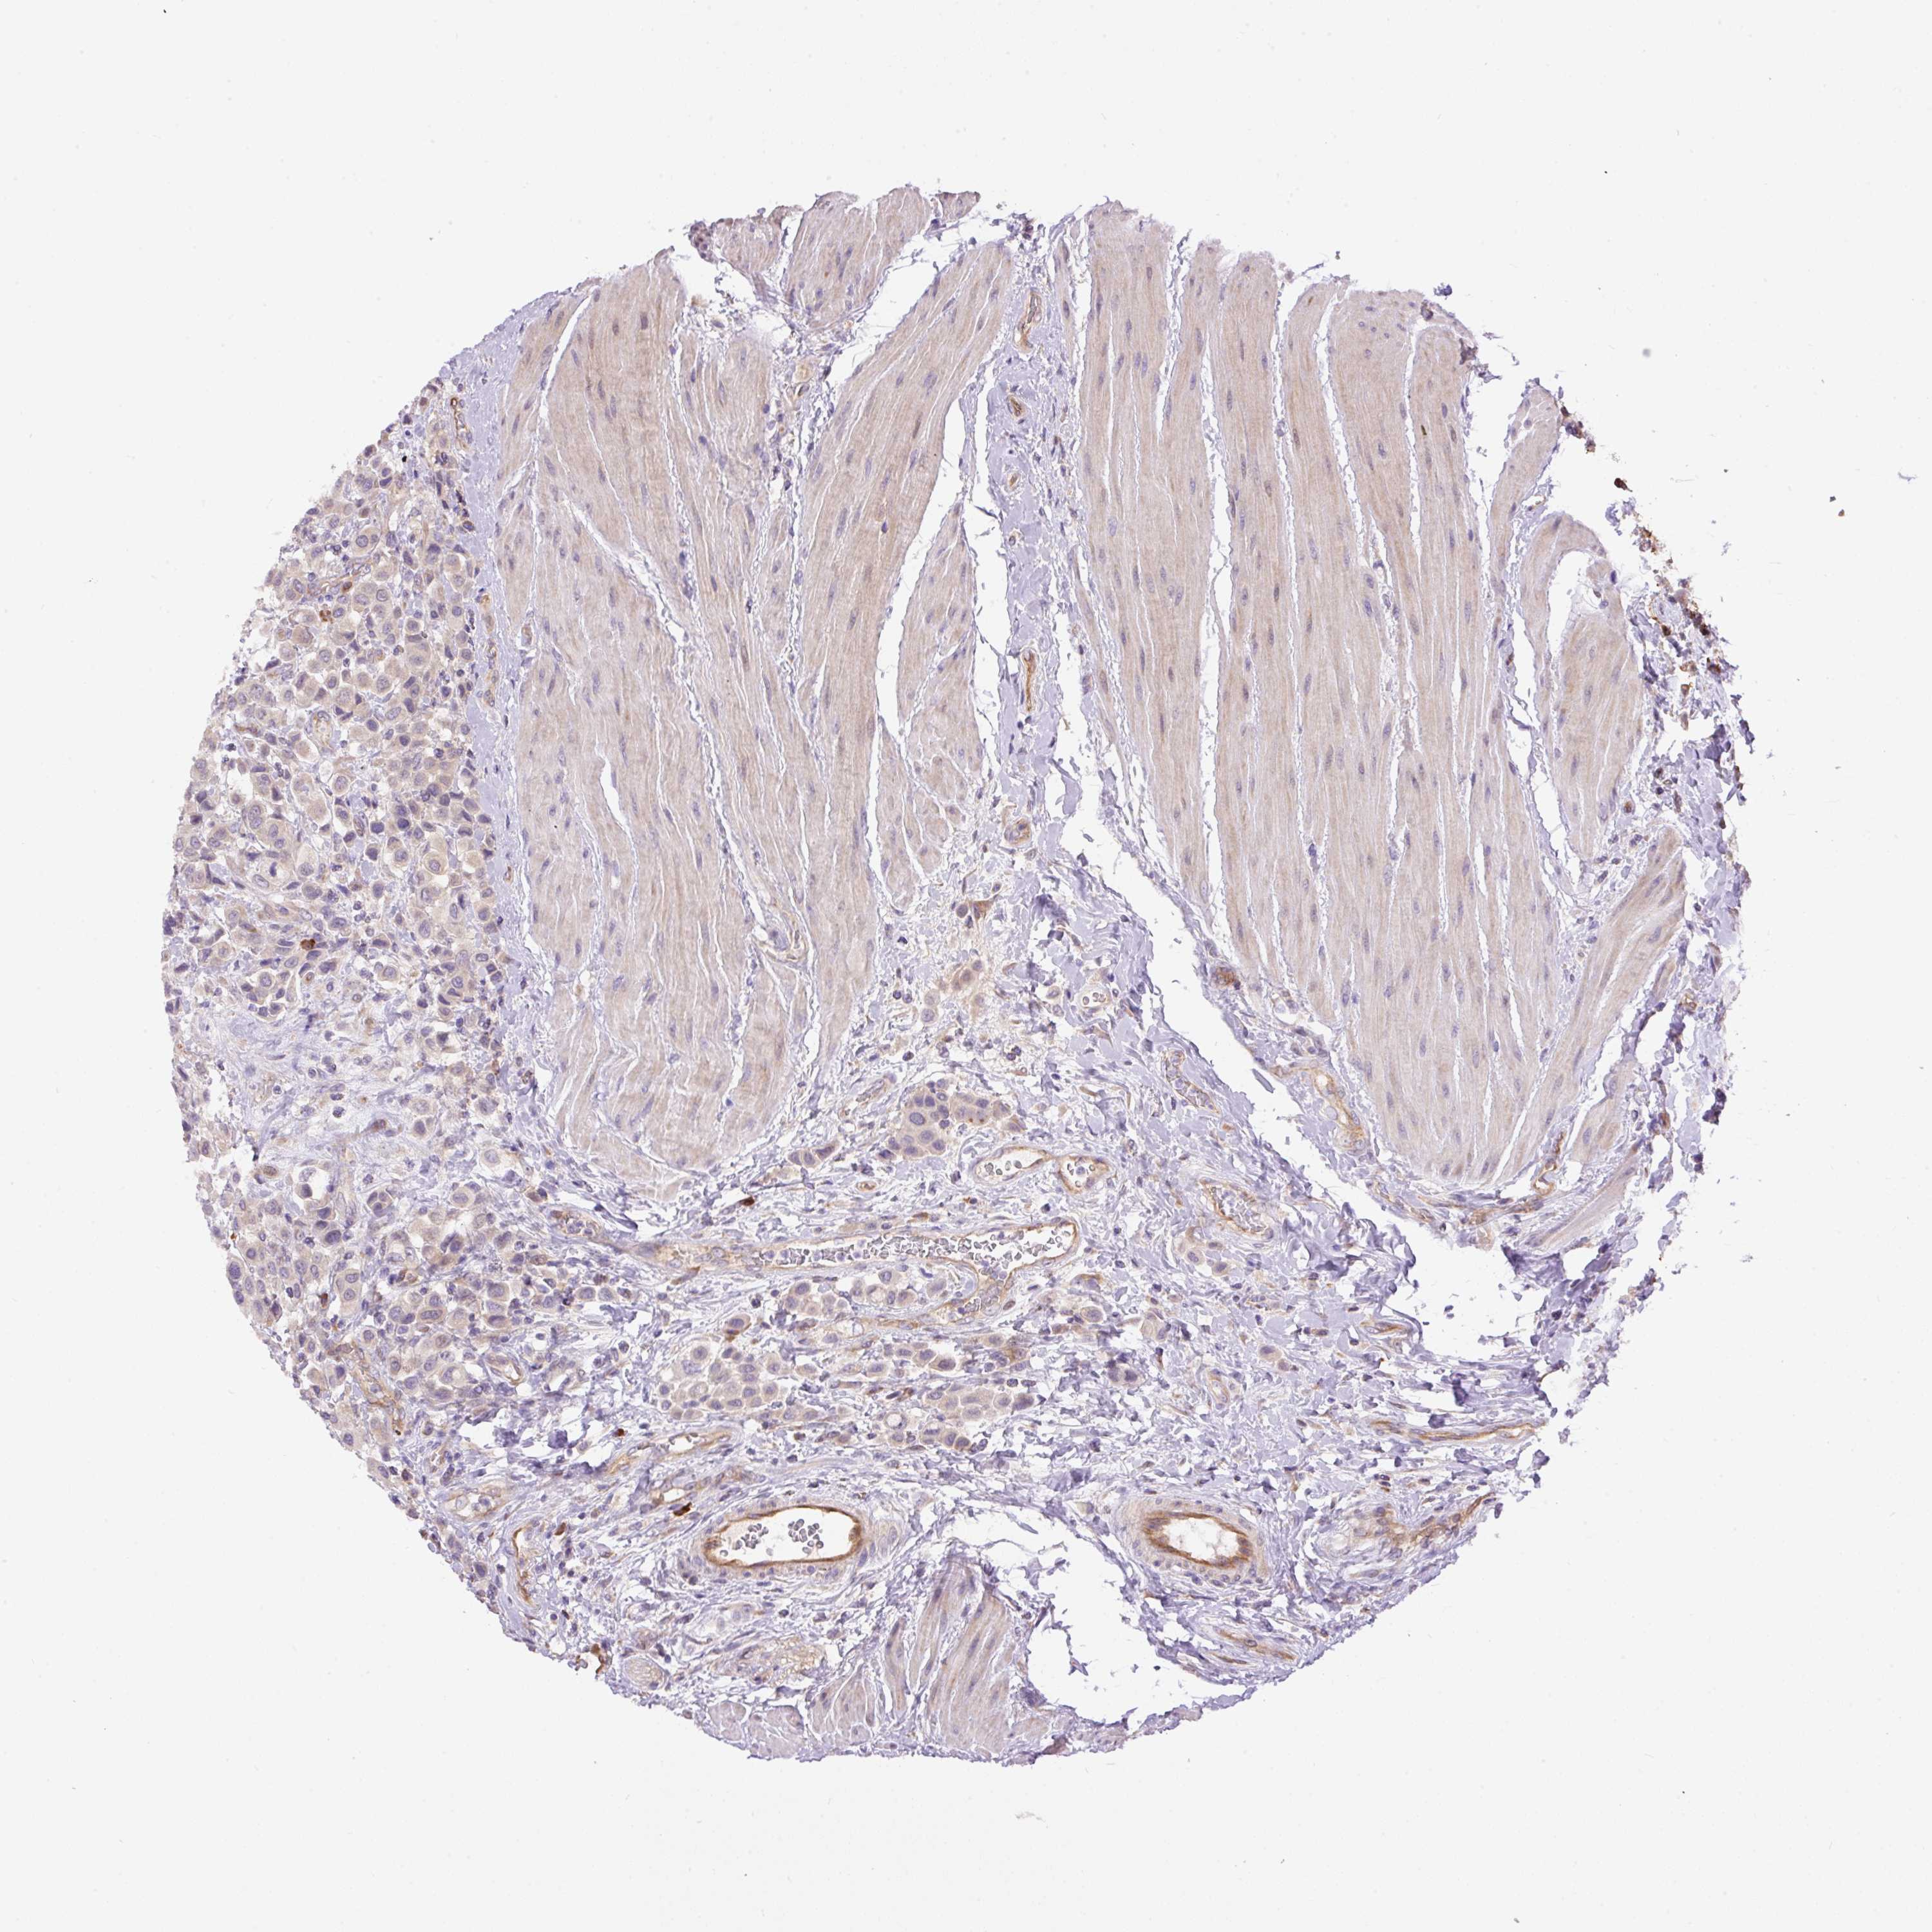

UROTHELIAL CANCER - Protein expressioni

A mouse-over function shows sample information and annotation data. Click on an image to view it in a full screen mode. Samples can be filtered based on level of antibody staining by selecting one or several of the following categories: high, medium, low and not detected. The assay and annotation is described here.

Note that samples used for immunohistochemistry by the Human Protein Atlas do not correspond to samples in the TCGA dataset.

Antibody stainingi

Antibody staining in the annotated cell types in the current human tissue is reported as not detected, low, medium, or high, based on conventional immunohistochemistry profiling in selected tissues. This score is based on the combination of the staining intensity and fraction of stained cells.

Each image is clickable and will lead to virtual microscopy that enables deeper exploration of all samples and also displays staining intensity scores, fraction scores and subcellular localization as well as patient and tissue information for each sample.

Antibody HPA043900

Antibody CAB004541

Staining

High

Medium

Low

Not detected

Intensity

Strong

Moderate

Weak

Negative

Quantity

>75%

75%-25%

<25%

None

Location

Nuclear

Cytoplasmic/membranous

Cytoplasmic/membranous,nuclear

Urothelial carcinoma, High grade

Urothelial carcinoma, Low grade